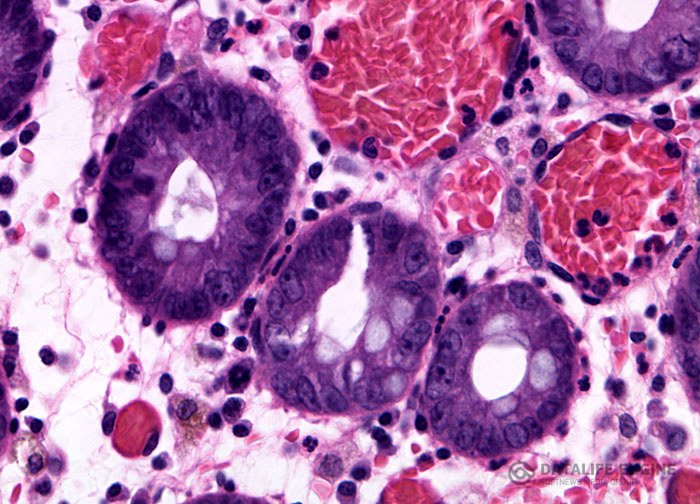

Неспецифический язвенный колит

Неспецифический язвенный колит — тяжелое заболевание, поражающее одинаково часто как женщин, так и мужчин. Причина язвенного колита до сих пор невыяснена, хотя теорий, пытающихся объяснить этнологию язвенного колита, выдвинуто немало. В начальной стадии болезни отмечаются обычно боли в животе и учащенный жидкий стул с примесью кровавой слизи или чистой крови, реже она начинается по типу острой дизентерии с повышением температуры, кровавым поносом, тенезмами. Иногда в клинике заболевания на первый план выступают явления интоксикации: боли в суставах, общая слабость, плохое самочувствие, лихорадка. В большинстве случаев наблюдаются исхудание, бледность кожных покровов. В испражнениях всегда имеются кровь и слизь. Течение болезни чаще всего хроническое, рецидивирующее. Болезнь нередко дает осложнения: прободение кишок с развитием перитонита, стенозы кишечника, тромбофлебиты, поражения поджелудочной железы, почек, миокарда. Из-за постоянной потери крови больные астеничны, истощены, страдают от малокровия. Прогноз заболевания неблагоприятный. В лечении колита любой этиологии решающим фактором является диета. Если принимать даже самые целебные в мире травы и не придерживаться правильной лечебной диеты — лечение будет неэффективным. Из рациона при всех видах колитов должны быть исключены в первую очередь отруби, даже в хлебе, так как они раздражают слизистую кишечника. Нельзя есть очень горячую и очень холодную пищу, пить большое количество жидкостей. Нежелательно употребление в пищу сырых овощей. Не следует, есть продукты, в которых содержится целлюлоза, поэтому шкурку и кожуру с фруктов надо счищать. Необходимо избегать жареной пищи, специй, кофе, всего того, что раздражает слизистую кишечника. В пищевом рационе должны содержаться все зерновые (за исключением отрубей), легкие и нежирные сорта мяса (курятина, баранина), все виды овощей (без семян, в вареном виде), йогурт, пудинги, кефир и простокваша, получерствый хлеб. Жиры в пище должны присутствовать в минимальном количестве. Слабительные из лечебных процедур должны быть исключены. При необходимости 1—2 раза в неделю можно сделать клизму.